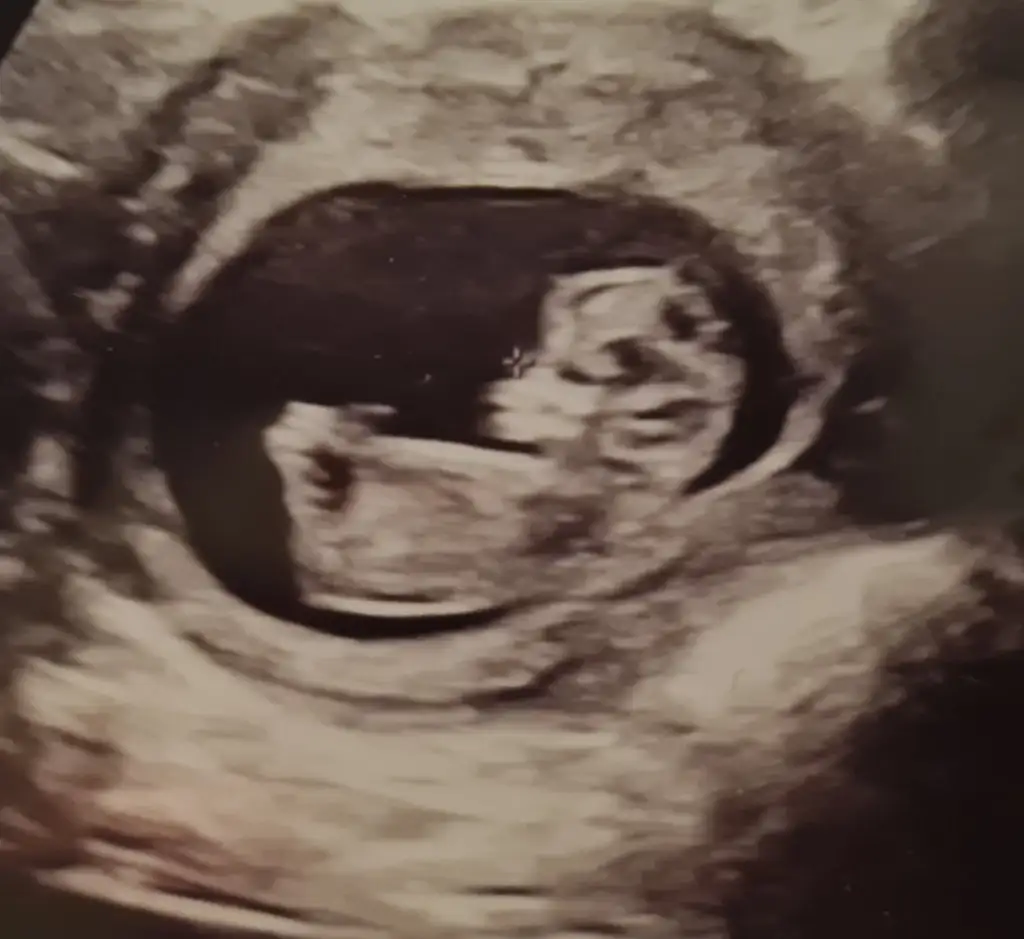

Benimde oluyor ağrılarım ara ara kasıkta ve karnımda. Doktor normal olduğunu söylemişti rahim büyüyor vucudumuz hazırlanıyorKızlar bugün tam 11. Haftaya girdik, bebiş incir büyüklüğündeymiş :) muhtemelen regl tarihim. Kaşıklarımda ince ince ağrılar var. Epeydir olmuyordu. Az korktum. Acaba adet tarihim diye mi ağrım oldu sizde de olmuş muydu ? Yarın doktor kontrolümüz var. Benimle aynı tarihli gele olan arkadaşım vardı. Geçen hafta bebişinin kalbi durmuş kürtaj olmuş ondan mı etkilendim noldu bilmiyorum bugün biraz kaygılıyım sanırım